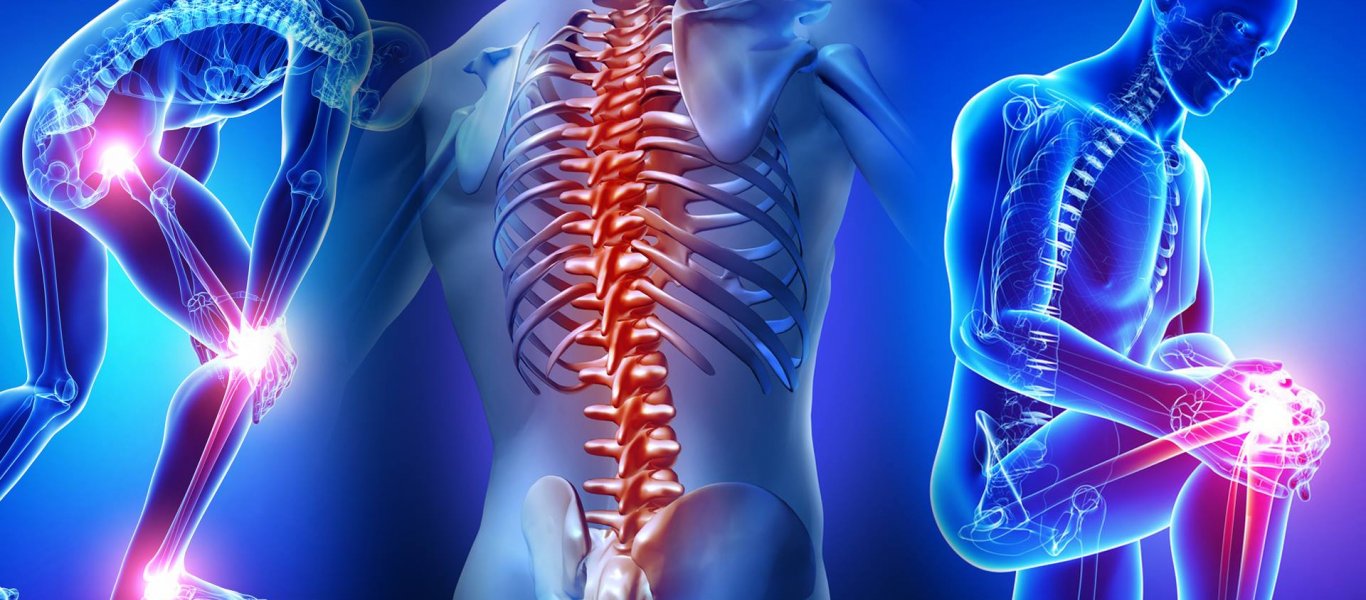

Οστεοπόρωση – Συμβουλές για την υγεία: Η δομή των οστών του ανθρώπου επηρεάζεται από τις τροφές που καταναλώνουν, οι άνθρωποι. Τα τρόφιμα είναι πλούσια σε ασβέστιο βιταμίνη D και θρεπτικά συστατικά. Μάλιστα, είναι ιδιαίτερα σημαντικά για τη υγεία των οστών.